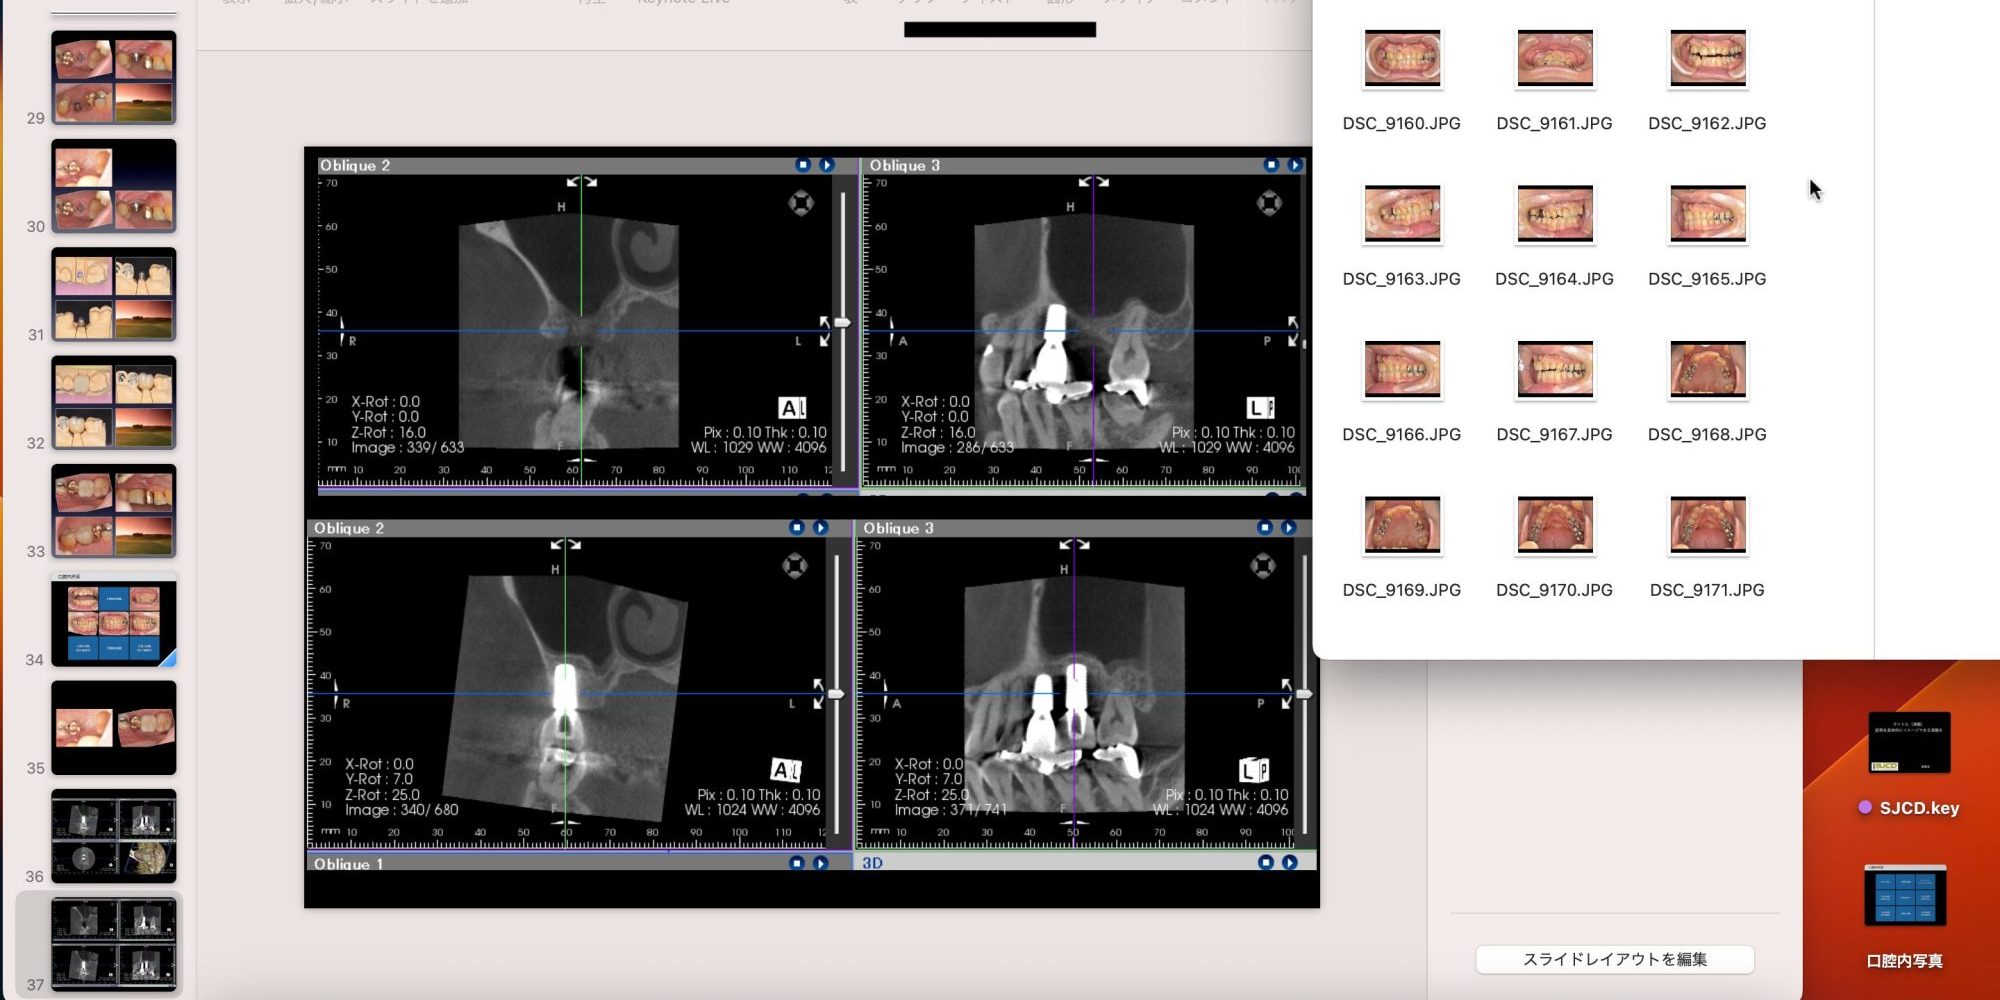

明日は症例発表があるので、発表スライドの作成です。もともと忘年会だけの予定でしたが、急遽「参加者は今年1年で1番自信のある症例を発表すること」とお達しがありました。忘年会でご飯を食べながら症例検討会をする予定みたいです。